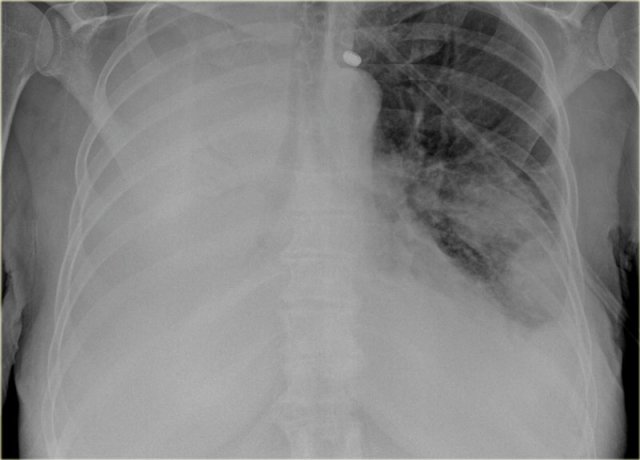

Pleural fluid

It takes about 200-300 ml of fluid before it comes visible on an CXR (figure).

About 5 liters of pleural fluid are present when there is total opacification of the hemithorax.

Total opacification of the right hemithorax in a patient with pleuritis carcinomatosa on both sides.

On the right there is only some air visible in the major bronchi creating an air bronchogram within the compressed lung.